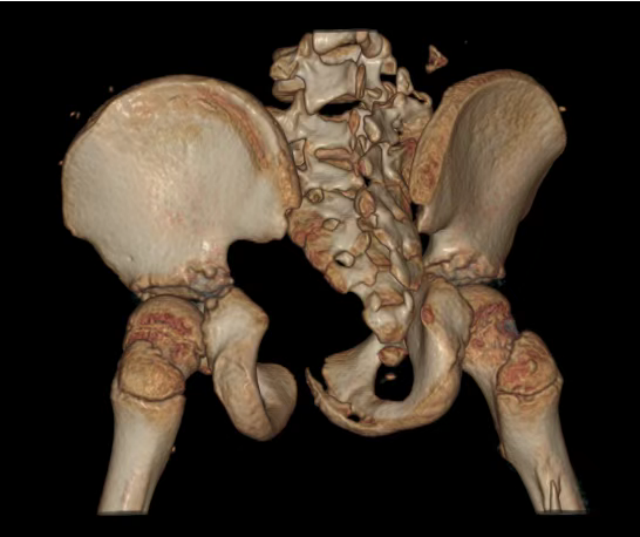

患儿术后影像,可见积血已消除、骨折已固定